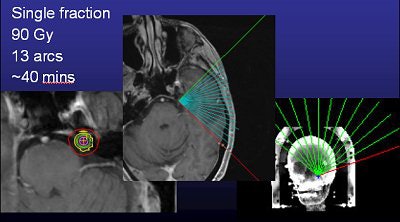

Murphy and colleagues at UCSD work with a linac system (Trilogy) and also perform gamma knife surgery. Time is one major difference between the two options in TN. A procedure with the Trilogy system takes about 30 to 40 minutes versus about two to three hours with the gamma knife, he said.

![]() |

| Same patient as above. CT scan is obtained in treatment position (FOV 35 cm, 1.25-mm slice thickness, no contrast). Images courtesy of Dr. Kevin Murphy and University of California, San Diego, department of radiation oncology. |

Murphy's list of linac shortcomings is, well, short. "I trained on (gamma knife). To train on a (Trilogy) system that was frameless and not proven was a hard thing to do. The dose is really high (90 Gy, four times the regular radiotherapy dose, but the same as gamma knife), and it's right next to the brain stem, so if you miss or the patient moves, you're going to fry the brain stem," he said.